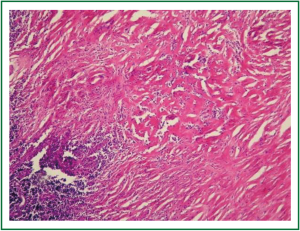

In physical examination, vital signs were normal, general and respiratory examination was unremarkable. Apart from a high fasting glucose level 177 mg/dL, eritrocyte sedimentation rate 48 mm/hr, liver function tests (AST: 73 IU/L, ALT: 92 IU/L), rutine laboratory analysis were normal. Respiratory function tests and oxygenation in room air were normal. The chest radiograph revealed prominence of right hilum and infiltration in the anterior segment of right upper lobe. A computed tomography scan revealed a 4 cm mass lesion in the right hilum and multiple mediastinal conglomerated lymph nodes (Figure 1). A PET/CT scan (Figure 2) demonstrated significantly increased activity (SUVmax: 9.74) at the right hilar mass lesion and right lower paratracheal (SUVmax: 3.57), subcarinal (SUVmax: 4.83), prevascular (SUVmax: 5.76) lymph nodes. Fiberoptic bronchoscopy showed mucosal distortion of right upper lobe. Pathologic examination of the mucosal biopsy revealed inflammation. Endobronchial ultrasound guided transbronchial needle biopsy from the hilar mass, right lower paratracheal and subcarinal lymph nodes revealed CD-45 positive normal lymphoid cells without any evidence of malignancy (Figure 3). Cervical mediastinoscopic biopsies of right lower paratracheal and subcarinal lymph nodes were undiagnostic. Diagnostic thoracotomy confirmed the diagnosis fibrosing mediastinitis. Hilar mass was a conglomerated lymph node showing dense hyalinized fibrous tissue with chronic inflammation (Figure 4). We administered 6 months of systemic corticosteroid and antituberculous therapy (Isoniazid, rifampicin, pirazinamid, ethambutol for two months and isoniazid, rifampicin for four months). A thorax tomography performed after discontinuation of therapy revealed similar findings with the postoperative thorax tomography.

In the endemic areas, the diagnosis is usually based on typical clinical and radiological findings (1). Mediastinoscopy or thoracotomy may be necessary to exclude malignancy and to confirm diagnosis (4). But in the presence of atypical features invasive diagnostic procedures are needed (7). It is usually difficult to make an accurate histopathological diagnosis using minimally invasive methods. Consequently many patients with fibrosing mediastinitis undergo surgical biopsy of the mediastinum to confirm the diagnosis and rule out a neoplasm. In this patient, there was a non-calcified right hilar mass lesion on CT scan. On PET/CT there was a high uptake of fluorodeoxyglucose both on the right hilar mass lesion and mediastinal lymph nodes. Endobronchial ultrasound guided mediastinal lymph node biopsies and mediastinoscopic biopsies were undiagnostic that the patient was sent to thoracotomy.